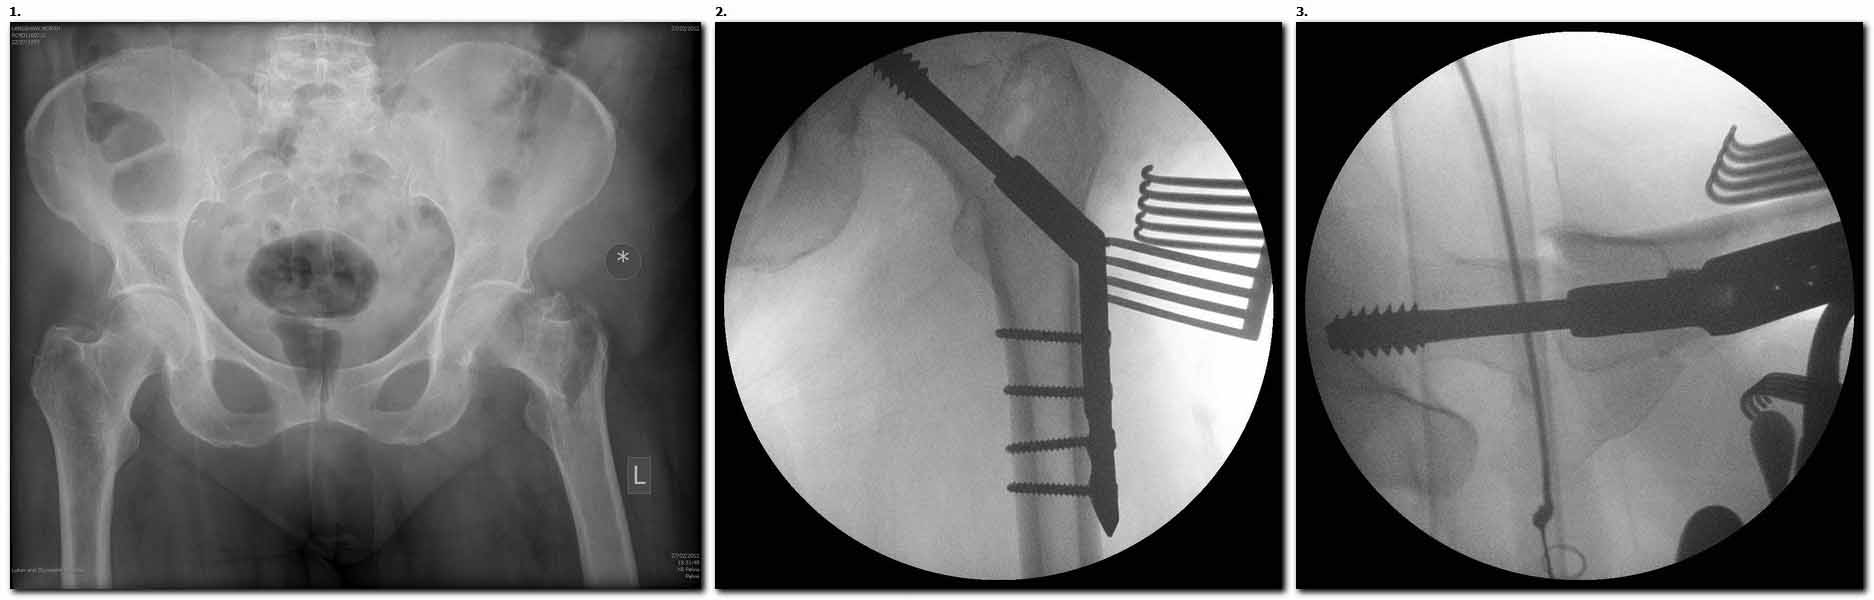

Банальный рутинный перелом чрезвертельной зоны лечимый DHS.

А по картинке можно сказать, что вроде бы все и неплохо. Предупредить миграцию шеечного винта при наружной ротации диафиза во время ходьбы достигают введением последнего поближе к переднему кортексу шейки. На Вашей картинке винт "смотрит" кзади. Отсутствие дополнительной боковой опоры для винта создает предпосылки для несостоятельности фиксации. (См. статью в прикреплении). Поэтому с ранней активизацией пациента в данном случае я бы подождал.

А пациент-то какой из себя?

При таком переломе мы бы тоже поставили вертельный гвоздь - на следующий день встать и побежать - чем не перспектива? На прямом снимке винт стоит замечательно, а коварный аксиальный подкачал, хотелось бы больше по центру шейки и головки завести. Да и смещение, какое-никакое, но есть. Посему - нагрузка 15 кг, а расширяли бы не раньше, чем через 5 недель.

Что касается данного перелома, то по-моему DHS или гамма - принципиальной разницы здесь конкретно нет - медиальная опора сохранена, при правильном исполнении можно ногу нагружать. Технически здесь выполнено на 3+, но если так же винт гаммы поставить - лучше не было бы.

Первые снимки показывают технические погрешности установки DHS. Не была достигнута репозиция, конечность в флексии и шейка в ротации. Сегодня все меньше обращают внимание на параметры для оценки репозиции (S контуры Lowell в обеих проекциях и Garden Alignment Index, в норме 155 и 180 градусов), хотя такие простые тесты помогли бы дорепонировать смещение. Винт находится сзади в головке, что при нагрузке поменяет вектор и вместо компрессии в линии перелома срежет головку-Cut Out!

В зависимости от дистанции линии перелома и латерального кортекса надо использовать разной длины barrel, т.е. конец баррели не должен доходить до пределов перелома. Здесь конец длинного ствола упирается в медиальный фрагмент, что мешает созданию компрессии, а более короткий barrel создал бы запас для компрессии. В боковой пластине вместо 4х можно было ограничится двумя шурупами, потому что головка шурупа в 4.5 мм выдерживает давление до 350 кг.

В заключение: чрезвертельные переломы можно лечить разными методами, включая наружные фиксаторы, но для начала надо определиться, какой это перелом? Стабильные переломы А1 (1-3), А2 (1) можно фиксировать DHS или гвоздем, а нестабильные переломы - гвоздями или современными пластинами для проксимального бедра. Трудным считается Reverse obliquity A3 (1) который из-за скоса перелома лучше удерживает Blade Plate, но современные гвозди неплохо зарекомендовали в лечении таких переломов.